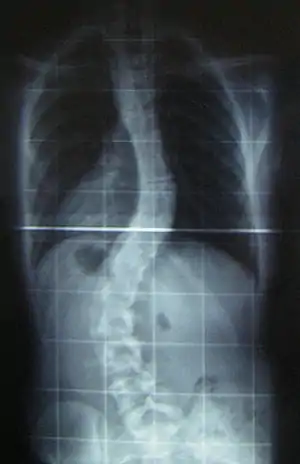

When scoliosis is suspected, weight-bearing, full-spine AP/coronal (front-back view) and lateral/sagittal (side view) X-rays are usually taken to assess the scoliosis curves and the kyphosis and lordosis, as these can also be affected in individuals with scoliosis. Full-length standing spine X-rays are the standard method for evaluating the severity and progression of scoliosis, and whether it is congenital or idiopathic in nature. In growing individuals, serial radiographs are obtained at 3- to 12-month intervals to follow curve progression, and, in some instances, MRI investigation is warranted to look at the spinal cord.[79] An average scoliosis patient has been in contact with around 50–300 mGy of radiation due to these radiographs during this time period.[80]

The standard method for assessing the curvature quantitatively is measuring the Cobb angle, which is the angle between two lines, drawn perpendicular to the upper endplate of the uppermost vertebra involved and the lower endplate of the lowest vertebra involved. For people with two curves, Cobb angles are followed for both curves. In some people, lateral-bending X-rays are obtained to assess the flexibility of the curves or the primary and compensatory curves.